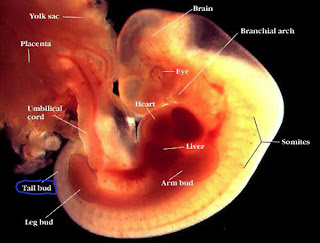

Aqui les presento un fragmento de "En el Vientre Materno", excelente documental transmitido por NatGeo!

EMBRIOGENESIS

En el momento de la concepción o fertilización, una sola célula comienza la existencia de un individuo, como resultado de la unión de espermatozoide y óvulo. Como paso previo a este encuentro, en el denominado período de gametogénesis, las células germinativas masculinas y femeninas experimentan cambios morfológicos y cromosómicos, mediante el proceso de meiosis.

La célula totipotencial, que será el origen de la vida de un nuevo individuo, llega a convertirse a lo largo de 266 a 280 días en trillones de células, las primeras de las cuales nacen del huevo fecundado como resultado de la división celular o mitosis.

La vida prenatal se divide en tres períodos:

1. el de fertilización o pre - implantación (primera semana)

2. el embrionario desde la segunda hasta la 8a semana

3. el fetal desde la 9ª semana hasta el nacimiento.

El período embrionario es el de organogénesis.

Desarrollo embriofetal y los períodos de mayor sensibilidad de los diversos órganos y sistemas

Entre la tercera y la octava semana, se desarrolla el período embrionario, o de organogénesis.

En él reconocemos como períodos de mayor sensibilidad, en el que diversos factores pueden alterar el normal desarrollo de los órganos, o de malformaciones mayores, a los siguientes:

Entre 3ª y 6ª semanas, sistema nervioso central.

Entre 3ª y 7ª semanas, corazón.

Entre 4ª y 7ª semanas, extremidades, tanto superiores como inferiores.

Entre 4ª y 8ª semanas, ojos.

Entre 7ª y 8ª semanas, dientes y paladar.

Entre 7ª y fin de la 8ª, con prolongación en la 9a semanas, genitales externos.

Entre 4ª y 9a, oído.

Luego de la 9a, comienza el período fetal, el de las malformaciones menores y defectos funcionales.